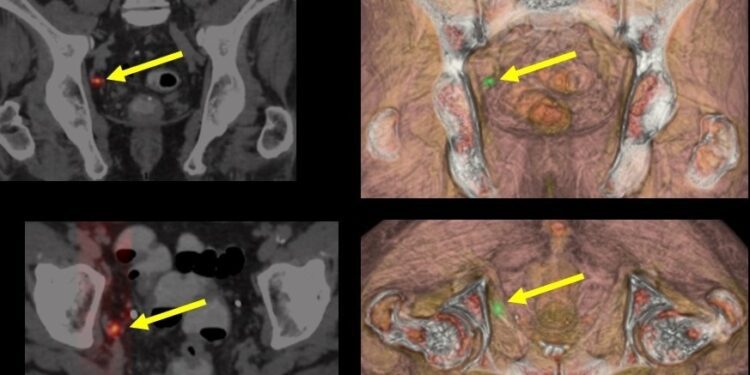

Otra tecnología avanzada que está ganando terreno en el tratamiento del cáncer de próstata es la protonterapia. Este tipo de radioterapia emplea protones, partículas subatómicas con propiedades físicas que permiten concentrar la dosis de radiación en el tumor y reducir el impacto en los tejidos sanos cercanos, lo cual disminuye los efectos secundarios. El doctor Miñana ha señalado que la experiencia clínica con protonterapia ha demostrado ser eficaz, minimizando o incluso evitando la radiación en órganos sanos circundantes. Esto reduce considerablemente los efectos secundarios relacionados con la función urinaria y sexual, dos aspectos críticos para la calidad de vida del paciente.

El doctor Mauricio Cambeiro, especialista del Área del Cáncer de Próstata del CCUN, enfatiza que la tecnología actual permite una administración de protonterapia con “máximo control y mínimo riesgo”, preservando tanto la funcionalidad eréctil como la urinaria en comparación con otros tratamientos más invasivos. Los equipos modernos para protonterapia permiten un tratamiento ambicioso en términos de curación y de reducción de complicaciones, lo que hace de esta opción una de las más avanzadas para el tratamiento de tumores de próstata.